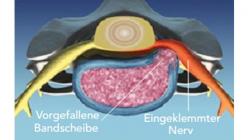

Bandscheiben sind flexible, faserknorpelige Verbindung, die als Stoßdämpfer zwischen den Wirbel dienen.

Mit zunehmendem Lebensalter kann es zu verschleißbedingten Rissen am äußeren Ring der Bandscheibe (Faserring) und zu einem Austritt des gallertartigen Kerns kommen. Dieser kann die benachbarten Nervenwurzeln oder das Rückenmark zusammendrücken und zu lokalen oder ausstrahlenden Schmerzen in den Armen und Beinen, ggf. auch mit Sensibilitätsstörungen und motorischen Ausfällen, führen.